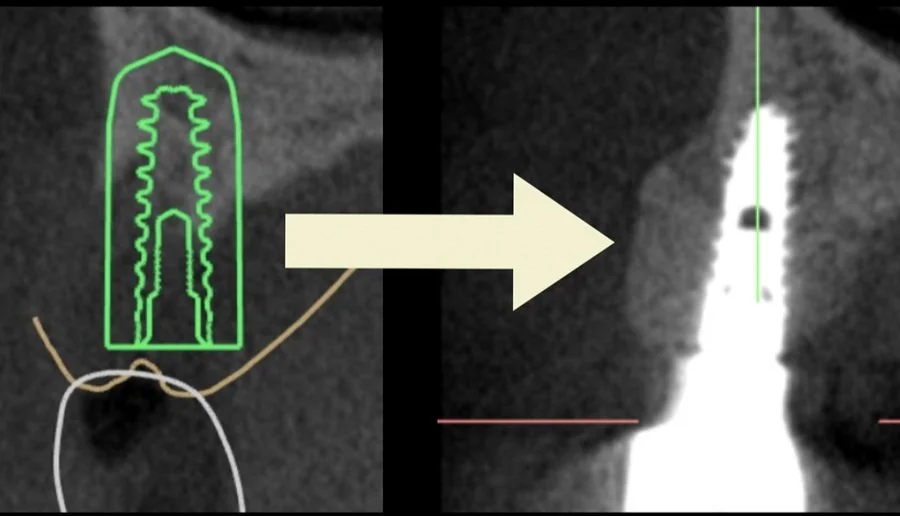

Many times, patients have no bone for implants and do not take kindly to a 1 year treatment plan. Traditionally, 6 months after bone grafting, implant is placed and the patient has to wait another 6 months until crown delivery. Furthermore, Vertical Ridge Augmentation is challenging and unpredictable.

Join us on October 04, 2023 to elevate your practice by learning how to do predictable implant placement and vertical ridge augmentation simultaneously. This cuts down the healing time by HALF and will save the patient pain and suffering from undergoing two surgeries.